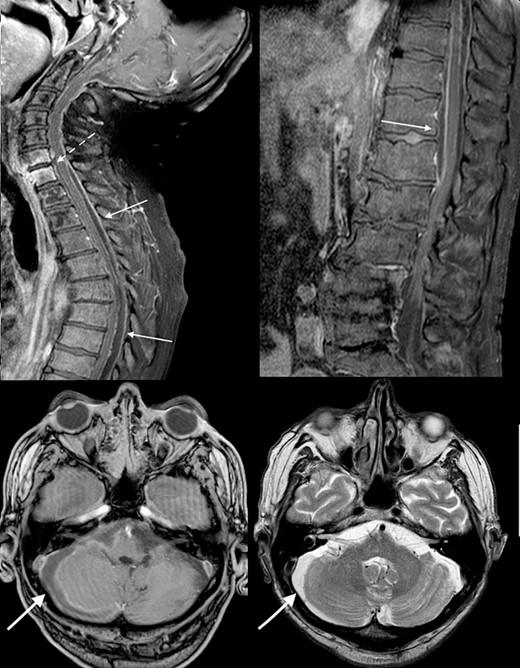

Urgent broad spectrum empiric antimicrobial therapy with Ceftriaxone, Metronidazole, and Vancomycin was initiated with guidance from Microbiology. Neurosurgical consultation advised MRI Brain and Whole Spine. In order to control the source of infection and obtain cultures and sensitivities, the TEP was removed under direct visualization (Fig. 2). A cuffed tracheostomy tube was inserted to prevent purulent discharge entering the trachea. MRI brain and whole spine revealed a vertebral C6-C7 osteomyelitis, subdural abscess, and epidural abscess within the spinal canal (Fig. 3). A recommendation for non-operative management with antimicrobial therapy was made by neurosurgery in light of the patient’s poor performance status and diffuse infection.

Initial MRI brain and whole spine demonstrating vertebral C6-C7 osteomyelitis (dotted arrow), subdural abscess within the cerebellum (bold arrow), and an epidural abscess within the spinal canal (arrow).